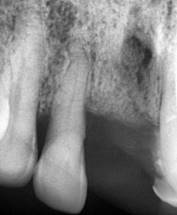

El paciente no refiere odontalgia, por lo que se presenta aparentemente asintomático al examen clínico. Dentro de las pruebas complementarias, se realizó la toma de una radiografía panorámica, donde se evidencio sobras radiolúcidas compatibles con reabsorción de la cresta ósea alveolar con patrón horizontal y vertical generalizado, también se visualizan sombras radiolúcidas alrededor de las raíces de las unidades dentales 1.2, 2.1 y 2.3, compatibles con procesos infecciosos y ensanchamiento del ligamento periodontal; además en la pieza 1.2 se complementó con una radiografía periapical en donde se observa una sombra radiopaca a nivel del tercio apical en el conducto radicular lo que podría indicar una posible calcificación y una sombra radiolúcida que rodea la raíz dental compatible con el posible ensanchamiento del ligamento periodontal; razón por la cual existe movilidad y menor soporte (Figura 2).

Para establecer el diagnóstico periodontal los valores obtenidos de la profundidad del sondaje, margen gingival, nivel de inserción, movilidad y línea mucogingival ayudaron a determinar que el paciente presenta periodontitis crónica severa generalizada según la clasificación de 1999 y endodónticamente al realizar pruebas de vitalidad a la pieza dental 1.2. Se presentó ausencia de respuesta lo que indica necrosis pulpar y periodontitis apical asintomática, de acuerdo a estos diagnósticos se le manifestó al paciente un plan de tratamiento basado en primera instancia la realización de una profilaxis, seguido de un raspado y alisado radicular con el fin de realizar una profunda eliminación de la placa alojada y mejorar el estado periodontal, el cual fue aprobado por el paciente. Posteriormente se evaluó la pieza 1.2, donde se determinó su extracción, ya que no fue posible realizar una endodoncia por el estado de afección y calcificación del conducto radicular, asimismo, el grado de comprometimiento del tejido periodontal avanzado, dando un pronóstico desfavorable. Se llevaron a cabo dos citas, en la primera se realizó una profilaxis, posteriormente raspado y alisado radicular.